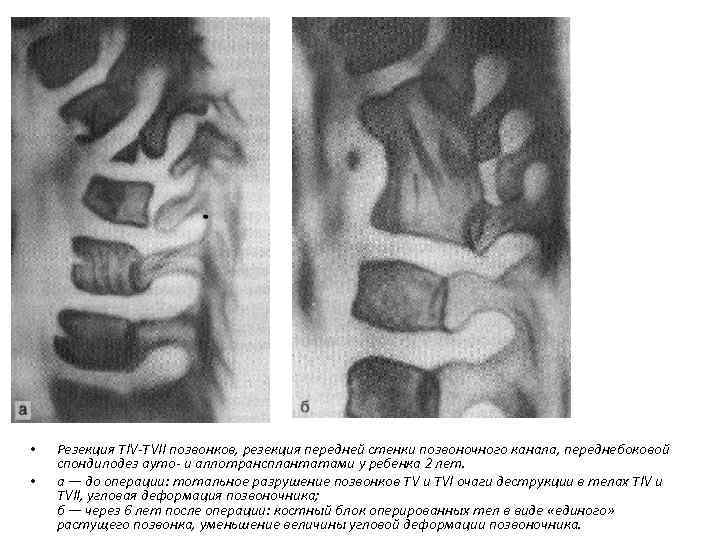

• • Резекция TIV-ТVII позвонков, резекция передней стенки позвоночного канала, переднебоковой спондилодез ауто- и аллотрансплантатами у ребенка 2 лет. а — до операции: тотальное разрушение позвонков ТV и ТVI очаги деструкции в телах ТIV и ТVII, угловая деформация позвоночника; б — через 6 лет после операции: костный блок оперированных тел в виде «единого» растущего позвонка, уменьшение величины угловой деформации позвоночника.

• • Резекция TIV-ТVII позвонков, резекция передней стенки позвоночного канала, переднебоковой спондилодез ауто- и аллотрансплантатами у ребенка 2 лет. а — до операции: тотальное разрушение позвонков ТV и ТVI очаги деструкции в телах ТIV и ТVII, угловая деформация позвоночника; б — через 6 лет после операции: костный блок оперированных тел в виде «единого» растущего позвонка, уменьшение величины угловой деформации позвоночника.